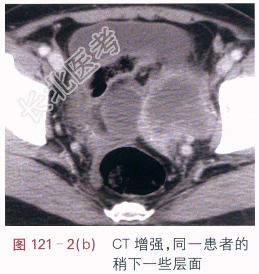

影像学资料如图121-1~图121-3所示。

读片分析:左侧附件区囊实性不规则形肿块,CT增强后实性部分的边缘呈明显强化,中心坏死部分强化不明显,未见肿大淋巴结和腹水征象。多平面重建后可见,左输尿管下段后累及,其中上段积水扩张。